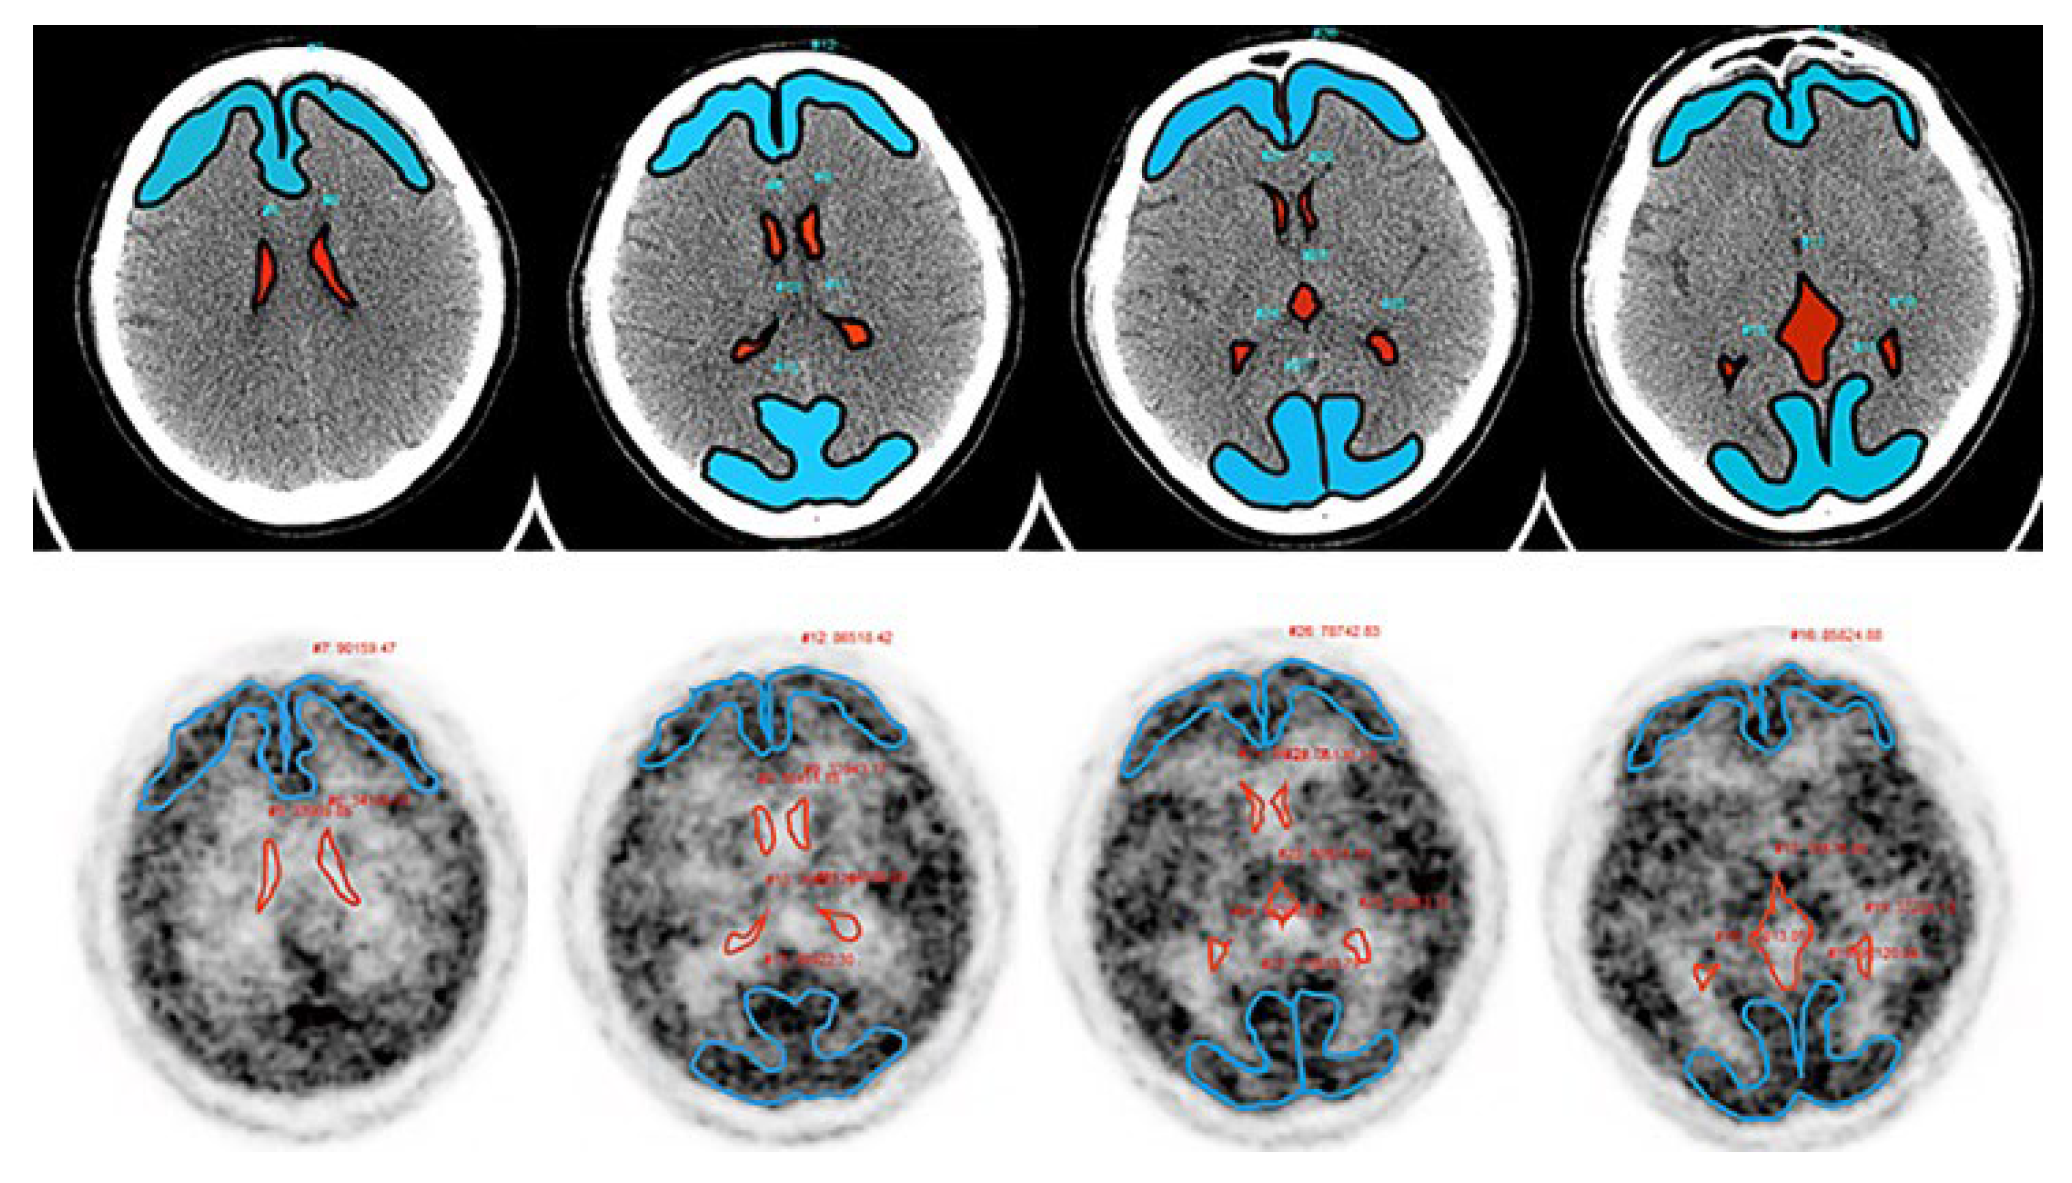

An intravenous bolus injection of 162–221 MBq [18F]flutemetamol (3.0–3.3 MBq/kg), produced using an automated synthesizer (FASTlab; GE Healthcare, Schenectady, NY, USA) was administered, and a 20-min PET scan in 3-dimensional statistic mode was started after 90 min in accordance with the imaging acquisition guidelines. The PET images scaled to 90% of the pons were visually assessed as either amyloid-positive or amyloid-negative on the basis of the training program instructions provided by GE Healthcare for the interpretation of [18F]flutemetamol images. A negative scan shows more radioactivity in the white matter than in the gray matter. Conversely, a positive scan shows gray matter radioactivity as intense as or exceeding that in the adjacent white matter in at least one of the five key regions (the posterior cingulate gyrus and precuneus, frontal cortex, lateral temporal cortex, parietal cortex, and striatum) (Figure 4).

Figure 4. The evaluation was performed according to the criteria defined by the manufacturer, which involved visual assessment of five regions: frontal cortex, PC/PCC, lateral-parietal, lateral temporal, and striatum. The final classification was either positive (unilateral binding in one or more cortical brain regions or striatum; (right)) or negative (predominantly white matter uptake; (left)).

The results are summarized in Table 1. In this study, participants were followed up at intervals of 2 years (range of interval periods: 2.0–2.8 years, mean ± SD: 2.2 ± 0.2 years). In the [15O]H2O PET examinations performed at the start and after 2 years, IR was 1.03 ± 0.21 and 1.02 ± 0.20, respectively, and DR was 1.74 ± 0.43 and 1.67 ± 0.47, respectively; both indices showed no significant changes over the 2-year period in the paired-sample t-test. On the other hand, as shown in Figure 4, the values for both indices were significantly lower than those in young controls (blue open circles and bars; IR = 1.38 ± 0.08 and DR = 2.12 ± 0.32) and significantly higher than those of the AD patients (red open circles and bars; IR = 0.73 ± 0.09 and DR = 0.86 ± 0.17).

At the initial [18F]flutemetamol PET examination, one of the 25 participants showed positive results and at the 2-year follow-up PET, two participants showed positive changes. All the other 22 participants showed negative results in both periods. The relationship between [15O]H2O PET and [18F]flutemetamol PET is shown in Figure 5. Red dots show the IR and DR results for the participant showing positive results in PET examinations conducted in both periods, and yellow dots show the results for the two participants who showed positive changes on follow-up PET. These three participants showed significantly low IR and DR values in both periods (IR, 0.60 ± 0.15 and 0.60 ± 0.13; DR, 1.24 ± 0.12 and 1.11 ± 0.10).

Figure 5. Relationship between intentional flow and β-amyloid accumulation. (A) Changes in IR and DR over 2 years. In the [15O]H2O PET examinations conducted at the start and after two years, IR was 1.03 ± 0.21 and 1.02 ± 0.20 and DR was 1.74 ± 0.43 and 1.67 ± 0.47, respectively, with both indices showing no significant changes over the 2-year period. The blue and red open circles and bars represented the mean and standard deviation of the results for young controls (YC) and AD patients (AD), respectively (IR: 1.38 ± 0.08 and 0.73 ± 0.09; DR: 2.12 ± 0.32 and 0.86 ± 0.17). Black dot: negative β-amyloid results on initial and follow-up PET examinations. Yellow dot: positive β-amyloid changes on follow-up PET examinations. Red dot: positive β-amyloid results on initial and follow-up PET examinations. (B) Changes in β-amyloid accumulation over 2 years. Upper: PET images showing a positive change (2 participants). Lower: PET images showing positive findings (1 participants).